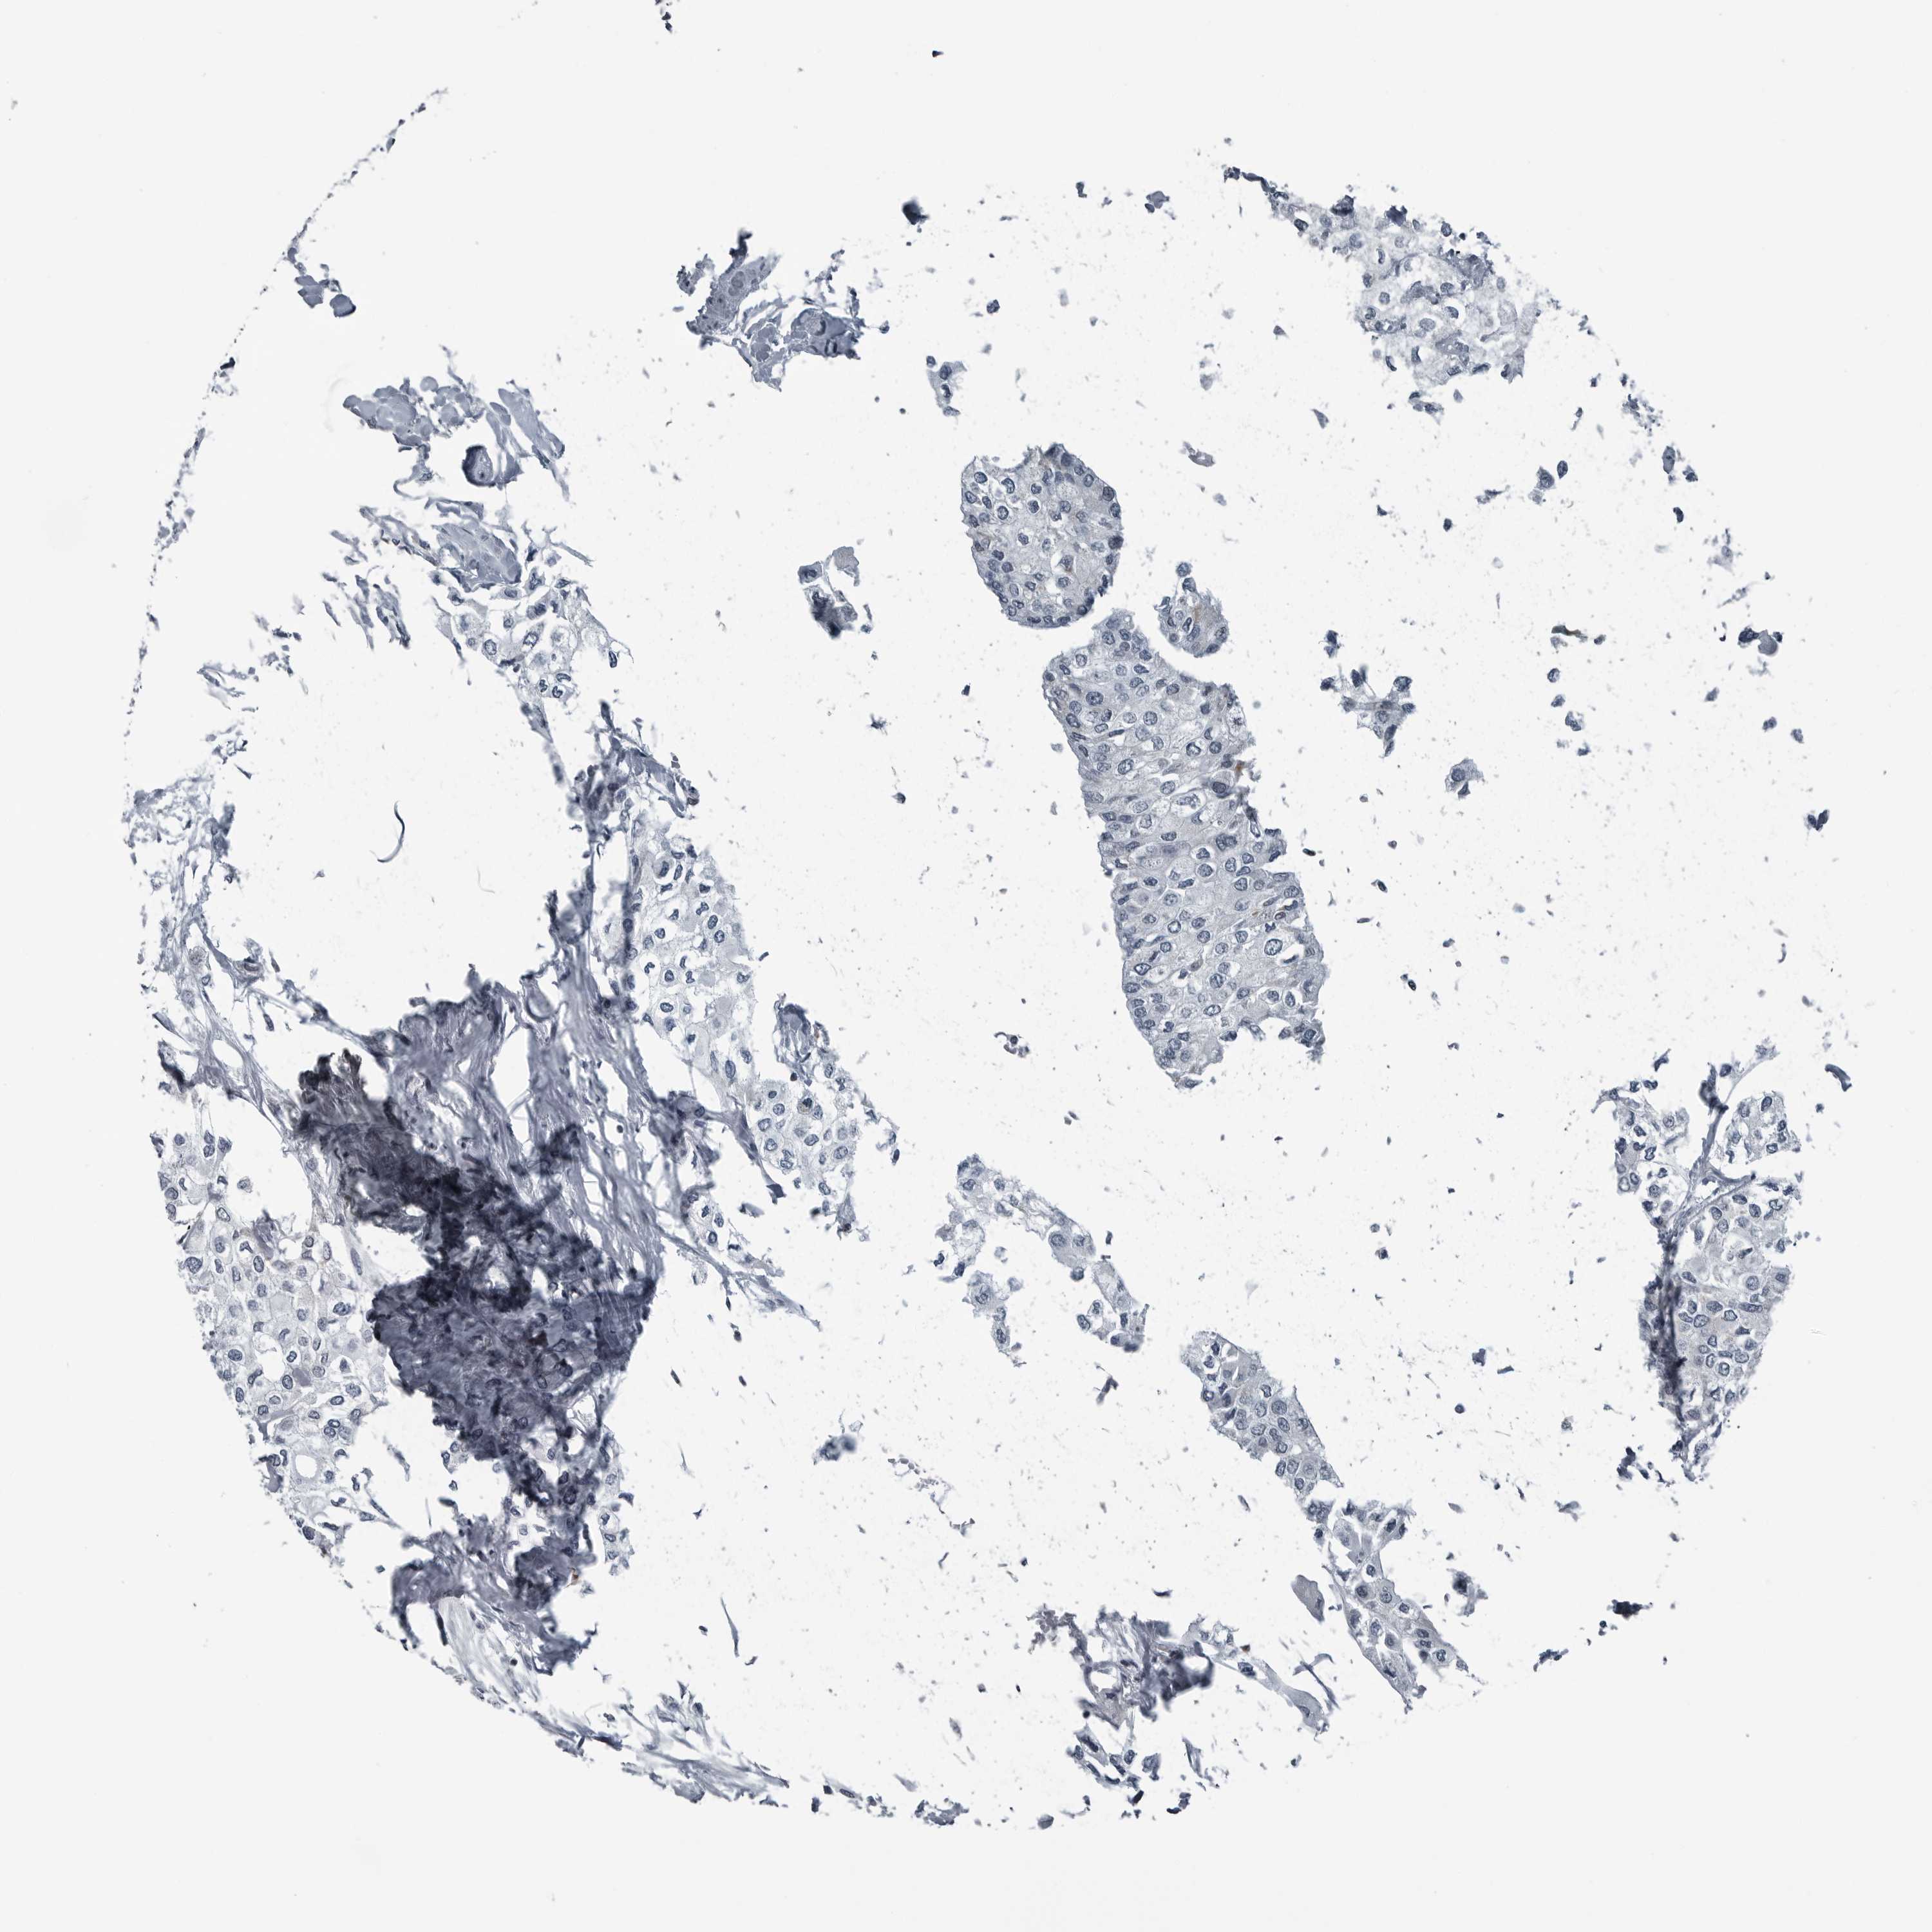

UROTHELIAL CANCER - Protein expressioni

A mouse-over function shows sample information and annotation data. Click on an image to view it in a full screen mode. Samples can be filtered based on level of antibody staining by selecting one or several of the following categories: high, medium, low and not detected. The assay and annotation is described here.

Note that samples used for immunohistochemistry by the Human Protein Atlas do not correspond to samples in the TCGA dataset.

Antibody stainingi

Antibody staining in the annotated cell types in the current human tissue is reported as not detected, low, medium, or high, based on conventional immunohistochemistry profiling in selected tissues. This score is based on the combination of the staining intensity and fraction of stained cells.

Each image is clickable and will lead to virtual microscopy that enables deeper exploration of all samples and also displays staining intensity scores, fraction scores and subcellular localization as well as patient and tissue information for each sample.

Antibody HPA027405

Antibody HPA027459

Antibody HPA027463

Staining

High

Medium

Low

Not detected

Intensity

Strong

Moderate

Weak

Negative

Quantity

>75%

75%-25%

<25%

None

Location

Nuclear

Cytoplasmic/membranous

Cytoplasmic/membranous,nuclear

Urothelial carcinoma, Low grade

Urothelial carcinoma, High grade